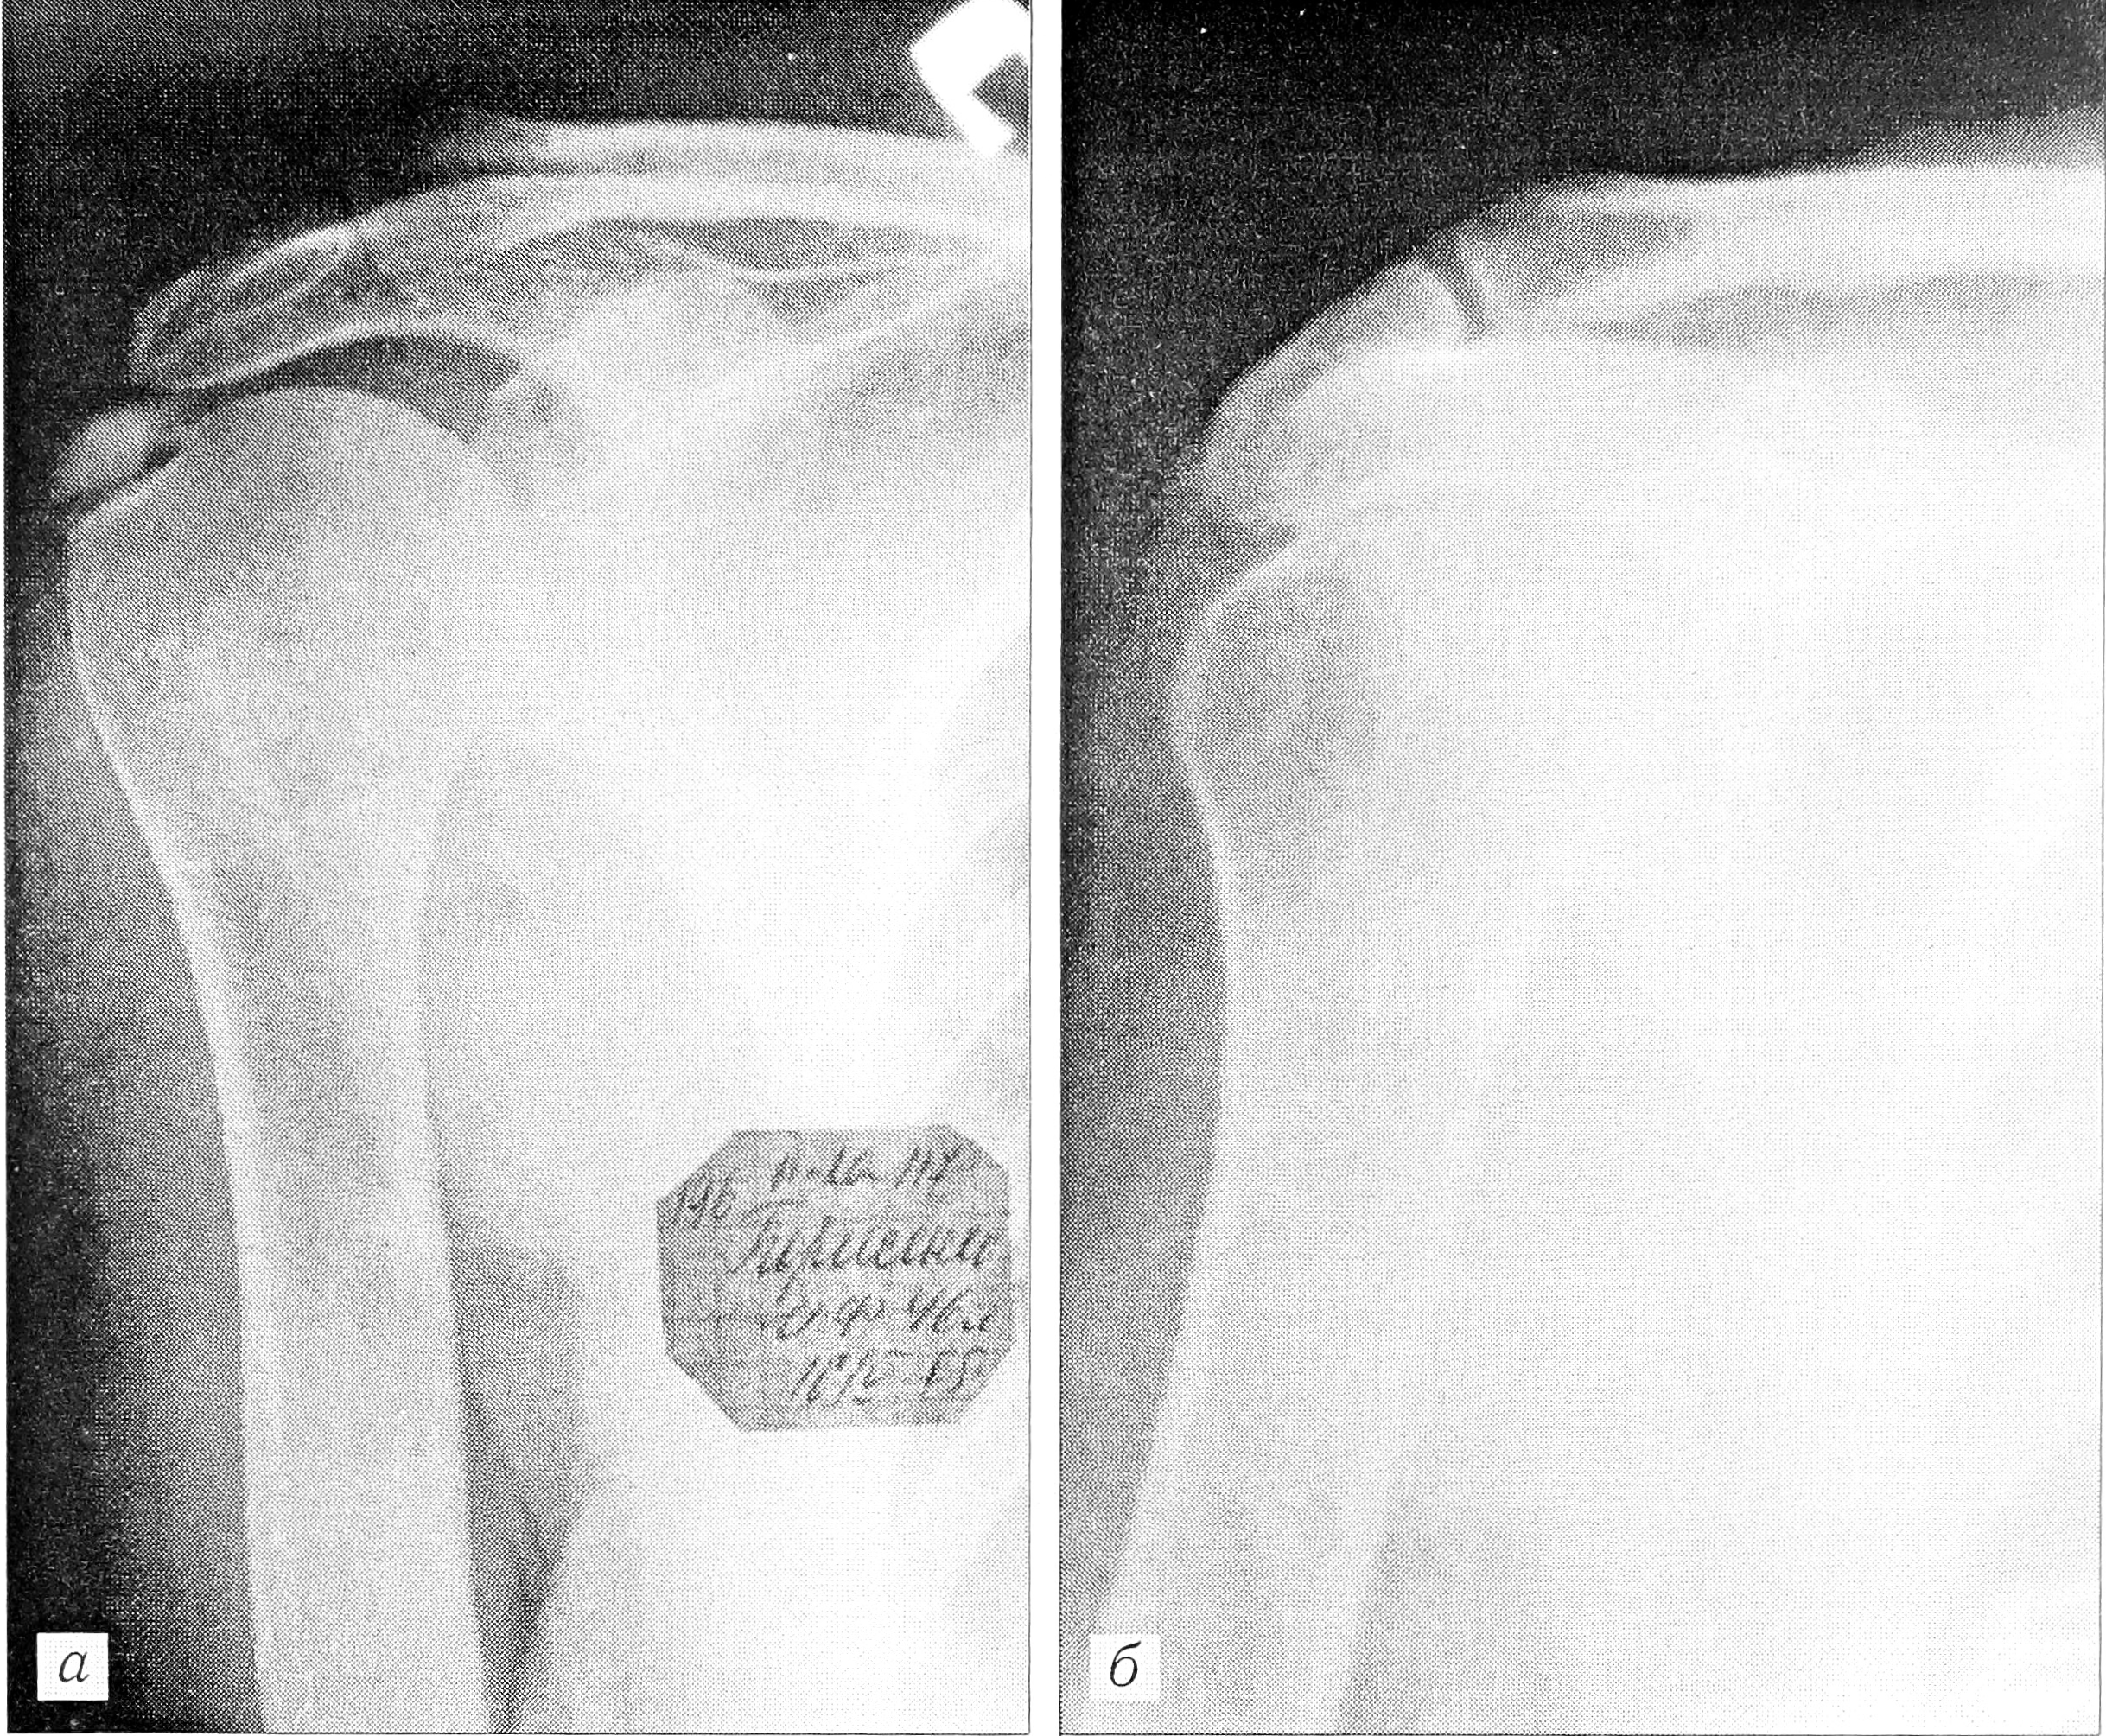

Лазеротерапия как самостоятельный или основной метод лечения с успехом применяется при плечелопаточном периартрите и периартрите других локализаций, в том числе осложненном калькулезным бурситом (рис. 3 на вклейке), при артрозе мелких суставов кисти, в начальных стадиях артроза крупных суставов, при остеохондрозе позвоночника, нарушениях трофики тканей конечности, длительно незаживающих раневых дефектах, постампутационных и посттравматических болевых синдромах, а также при многих других патологических процессах, обусловленных нарушением нейрорегуляции трофики тканей. Методики лечения подробно изложены в методических материалах и рекомендованы к широкому применению Минздравом СССР и Минздравмедпромом РФ [2, 5].

Рис. 3. Рентгенограммы больного 46 лет с хроническим рецидивирующим плечелопаточным периартрозом, калькулезным бурситом.

а — до лечения; б —после курса лазеротерапии: рассасывание оссификата капсулы плечевого сустава.